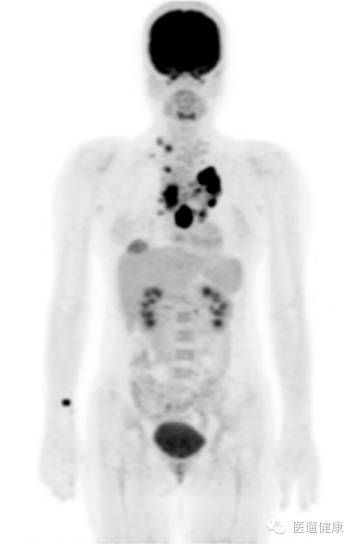

PET/CT协助临床对各类恶性肿瘤进行分期

上图是PET/CT通过一次显像获得的全身图像,图中黑色的部分清晰地显示了高代谢病灶,这使得医生一目了然地掌握病患原发肿瘤以及全身的转移情况,再结合CT, 医生可以对病灶精确定位,并排除一些生理性高代谢灶或良性病变,这样,可以再在最大程度上保证了肿瘤分期的准确性。

PET/CT显像在肿瘤分期中的价值在三方面:

①通过探查到形态学上未发生变化的病灶而影响分期。

②通过改变分期来影响肿瘤患者的治疗方案。

③18F-FDG PET/CT显像是公认的肿瘤分期的首选方法,尤其在肿瘤的N、M(淋巴转移和远处转移)分期方面有绝对优势。